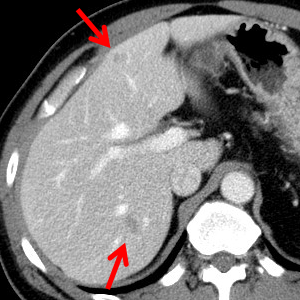

CT¿¡¼­ ÀúÀ½¿µÀÇ Á¶¿µÁõ°­ÀÌ ¾È µÇ´Â 2 cm ÀÌÇÏ ´Ù¹ß¼º Á¾±«·Î º¸À̸ç fuzzy margin, subtle hypoattenuation, non-spherical shape µîÀÌ Æ¯Â¡ÀÔ´Ï´Ù. ½Ã°£ÀÌ Áö³ª¸é ÀúÀý·Î »ç¶óÁöÁö¸¸ °£È¤ follow-up¿¡¼­ º´¼ÒÀÇ À§Ä¡°¡ ´Þ¶óÁý´Ï´Ù. ±×·¡¼­ À̸§ÀÌ visceral larva migransÀÔ´Ï´Ù.

CT¿¡¼­´Â ÁÖ·Î ÀúÀ½¿µÀÇ Á¶¿µÁõ°­ÀÌ ¾È µÇ´Â 2 cm ÀÌÇÏÀÇ ´Ù¹ß¼º Á¾±«·Î º¸À̸ç fuzzy margin, subtle hypoattenuation, non-spherical shape µîÀÌ Æ¯Â¡À̶ó°í ÇÕ´Ï´Ù. ½Ã°£ÀÌ Áö³ª¸é ÀúÀý·Î »ç¶óÁöÁö¸¸ °£È¤ follow-up¿¡¼­ º´¼ÒÀÇ À§Ä¡°¡ ´Þ¶óÁö´Â °æ¿ìµµ ÀÖ½À´Ï´Ù (±×·¡¼­ À̸§ÀÌ visceral larva migransÀÔ´Ï´Ù).